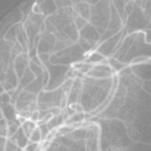

The rapid and accurate direct multi-frame interpolation method for Digital Subtraction Angiography (DSA) images is crucial for reducing radiation and providing real-time assistance to physicians for precise diagnostics and treatment. DSA images contain complex vascular structures and various motions. Applying natural scene Video Frame Interpolation (VFI) methods results in motion artifacts, structural dissipation, and blurriness. Recently, MoSt-DSA has specifically addressed these issues for the first time and achieved SOTA results. However, MoSt-DSA's focus on real-time performance leads to insufficient suppression of high-frequency noise and incomplete filtering of low-frequency noise in the generated images. To address these issues within the same computational time scale, we propose GaraMoSt. Specifically, we optimize the network pipeline with a parallel design and propose a module named MG-MSFE. MG-MSFE extracts frame-relative motion and structural features at various granularities in a fully convolutional parallel manner and supports independent, flexible adjustment of context-aware granularity at different scales, thus enhancing computational efficiency and accuracy. Extensive experiments demonstrate that GaraMoSt achieves the SOTA performance in accuracy, robustness, visual effects, and noise suppression, comprehensively surpassing MoSt-DSA and other natural scene VFI methods. The code and models are available at https://github.com/ZyoungXu/GaraMoSt.